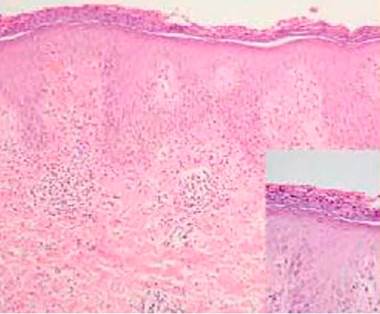

Al examen físico se encuentra el paciente con placas eritematosas, circunscritas con bordes elevados y descamación gruesa que comprometen toda la superficie corporal (figs. 1a y 2a). En el cuero cabelludo, placas con descamación adherente, tipo falsa tiña amiantácea, extendiéndose más allá del borde de implantación anterior del pelo. En algunas uñas se observa onicólisis, hiperqueratosis subungular y signo de la gota de aceite (fig. 3a). Se realiza biopsia de piel en la cual se evidencia paraqueratosis y pústulas intracórneas (fig. 4), hallazgos compatibles con psoriasis. Se calcula un PASI (siglas en inglés para índice de severidad de psoriasis según área) de 48. Con estos nuevos hallazgos, se realizan estudios imagenológicos, encontrando en radiografía de manos osteopenia difusa de los huesos del carpo derecho con disminución de espacios articulares interfalángicos proximales del dedo 5 en forma bilateral y del dedo 3 de la mano derecha con mínimo edema de tejidos blandos, en radiografía de columna cervical fusión de las articulaciones facetarias C7 a T1 y, en los pies, subluxación metacarpofalángica de todos los dedos y deformidad en valgo (fig. 5a). La tomografía axial computarizada de las articulaciones sacroilíacas muestra fusión de los 2/3 inferiores y esclerosis de 1/3 superior (fig. 6a).

Figura 4 Biopsia de piel con aumento 4X: epidermis acantósica con patrón psoriasiforme. Aumento 40X: estrato córneo con hiperqueratosis con paraqueratosis, microabscesos de Munro, disminución de estrato granuloso y neovascularización en dermis papilar.